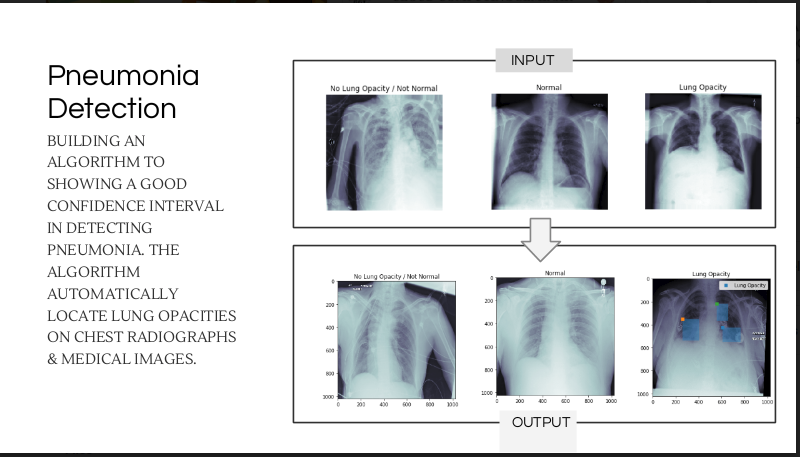

Pneumonia Detection

• Deep learning • Python